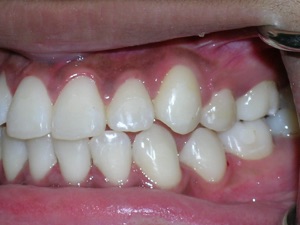

Some nice after photos.

Look at the before and after of the second molar on the right side.